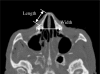

The nasal bone is among the most frequently broken facial bone due to all types of trauma and is the most frequently fractured facial bone due to motor vehicle collisions. This study reports the results of anterior-posterior impacts performed on male cadavers using a free-falling impactor with a flat impacting surface. The force at fracture onset was determined using an acoustic emission sensor. These non-censored data were utilized in parametric and non-parametric techniques to determine a relationship between applied force and fracture risk. Based on these analyses a 50% risk of fracture corresponded to an applied force of approximately 450 to 850 N. There was no correlation between fracture force and anthropometric measures of the nasal bone. Interestingly, age had a statistically significant relationship with the risk of nasal bone fracture. This study demonstrates the need for a non-censored measure of fracture occurrence when evaluating structures that can continue to support load after fracture onset.